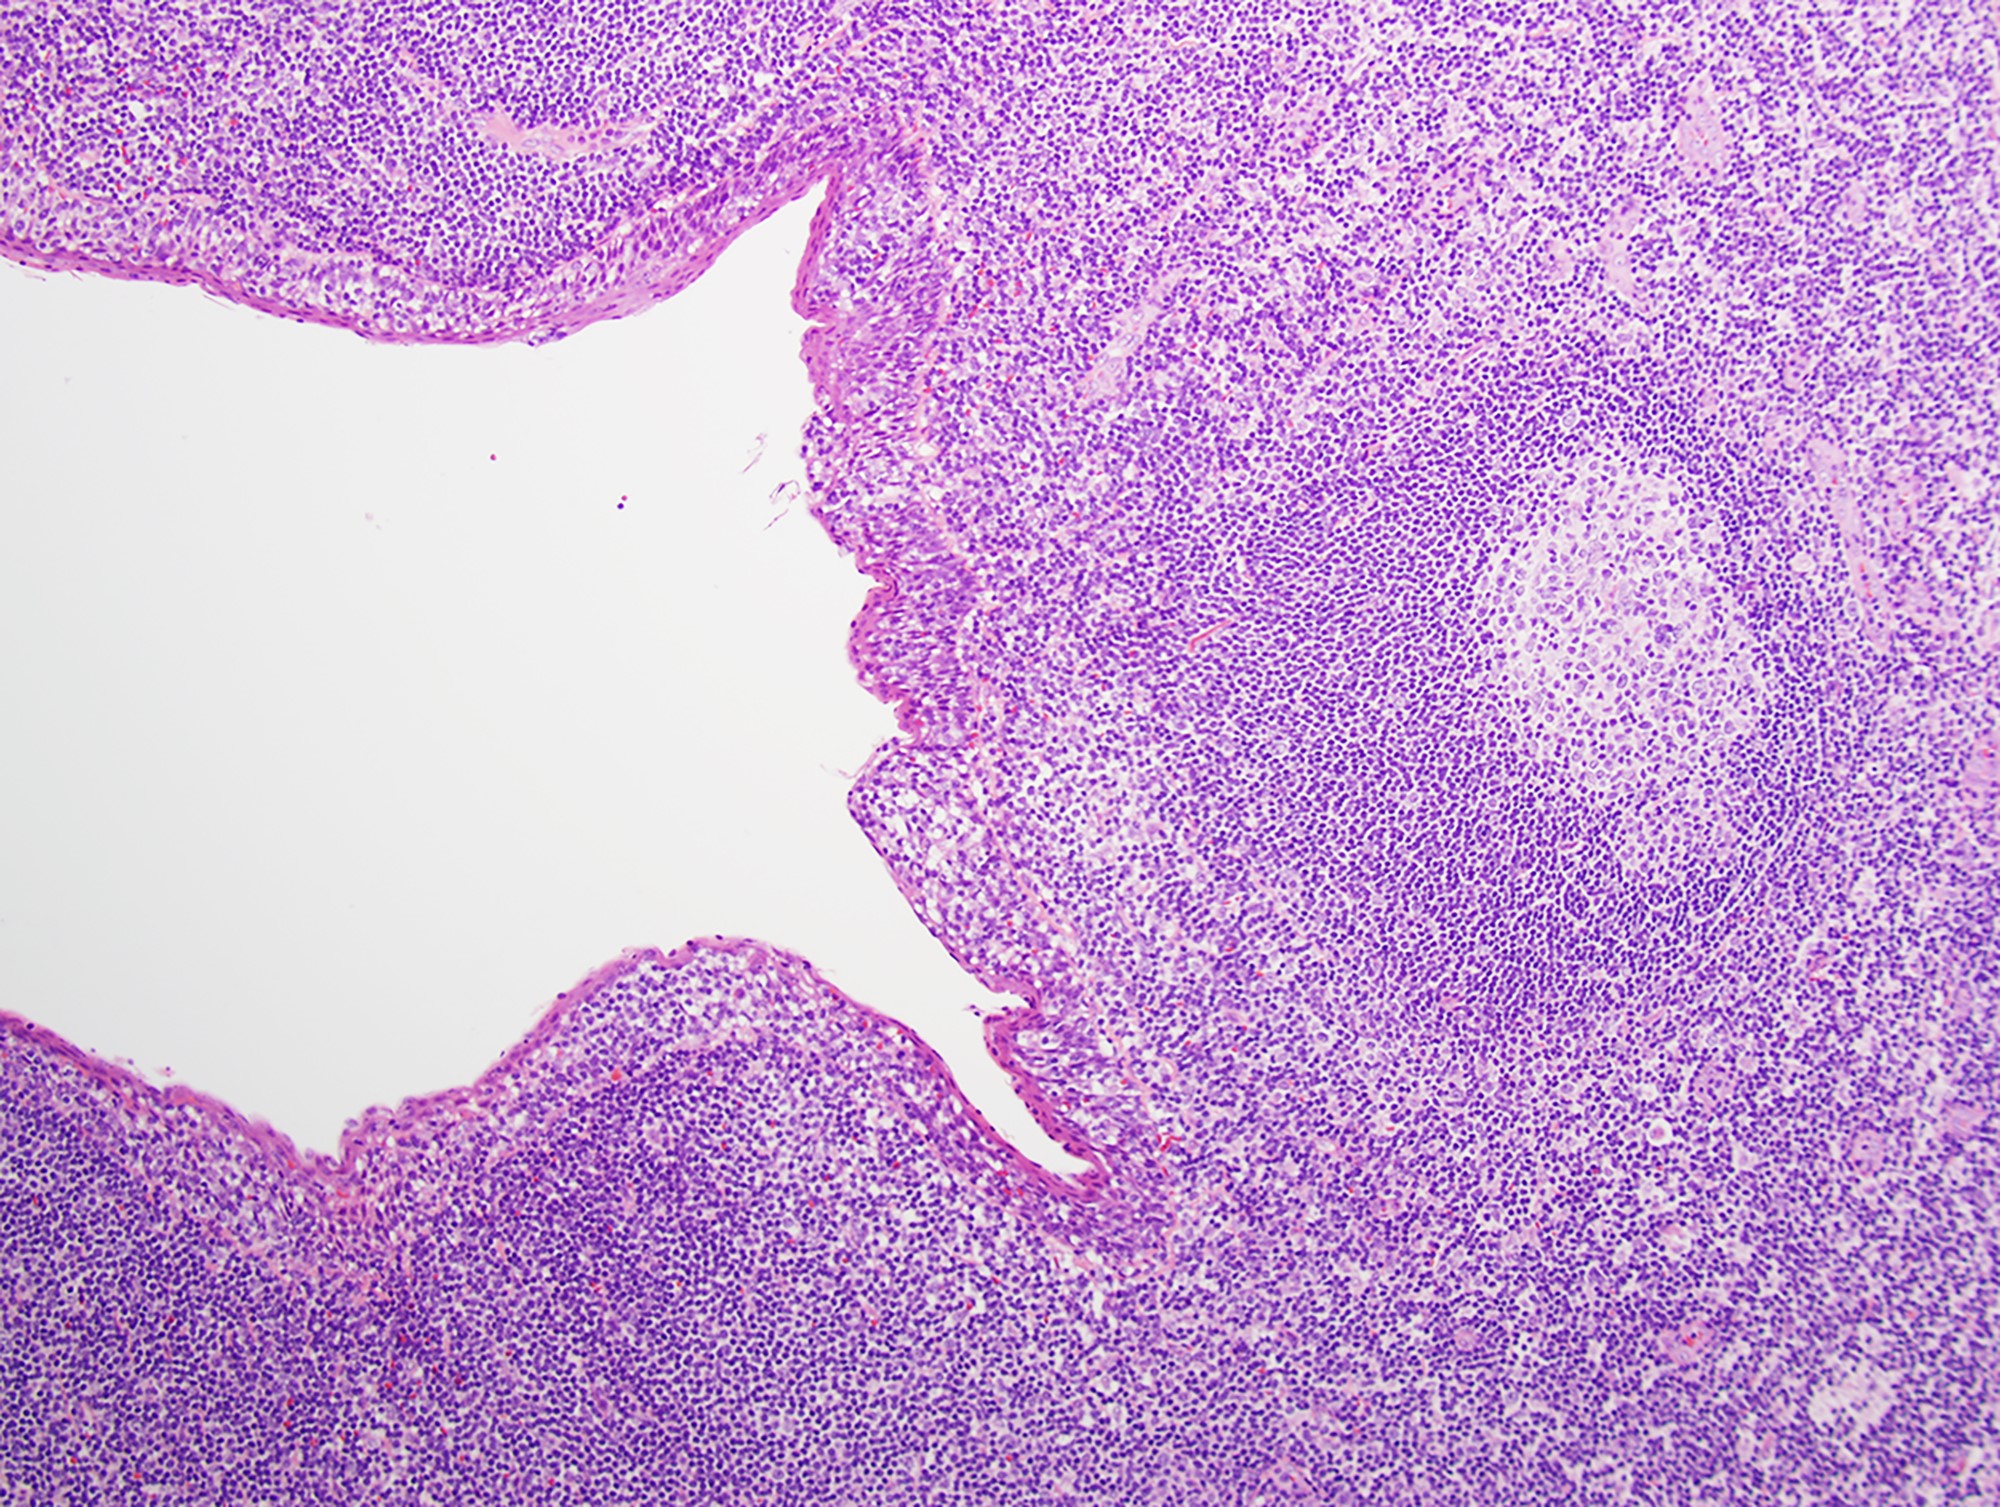

- Most cases show a unilocular cyst with a thin stratified squamous lining

- Ciliated, cuboidal or columnar epithelial lining is seen in rare cases

- Epithelium is surrounded by dense polymorphous lymphoid tissue with germinal centers and sinusoidal spaces

- Lymphocytes frequently permeate the epithelial cyst lining cells

Microscopic (histologic) images